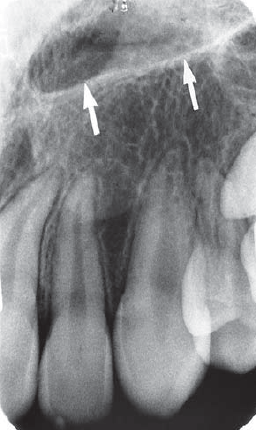

6. Which anatomical structure indicated by black arrow?

7. What is the anatomical structure indicated by arrow in this radiograph?

8. What is indicated by arrow in this xray ?